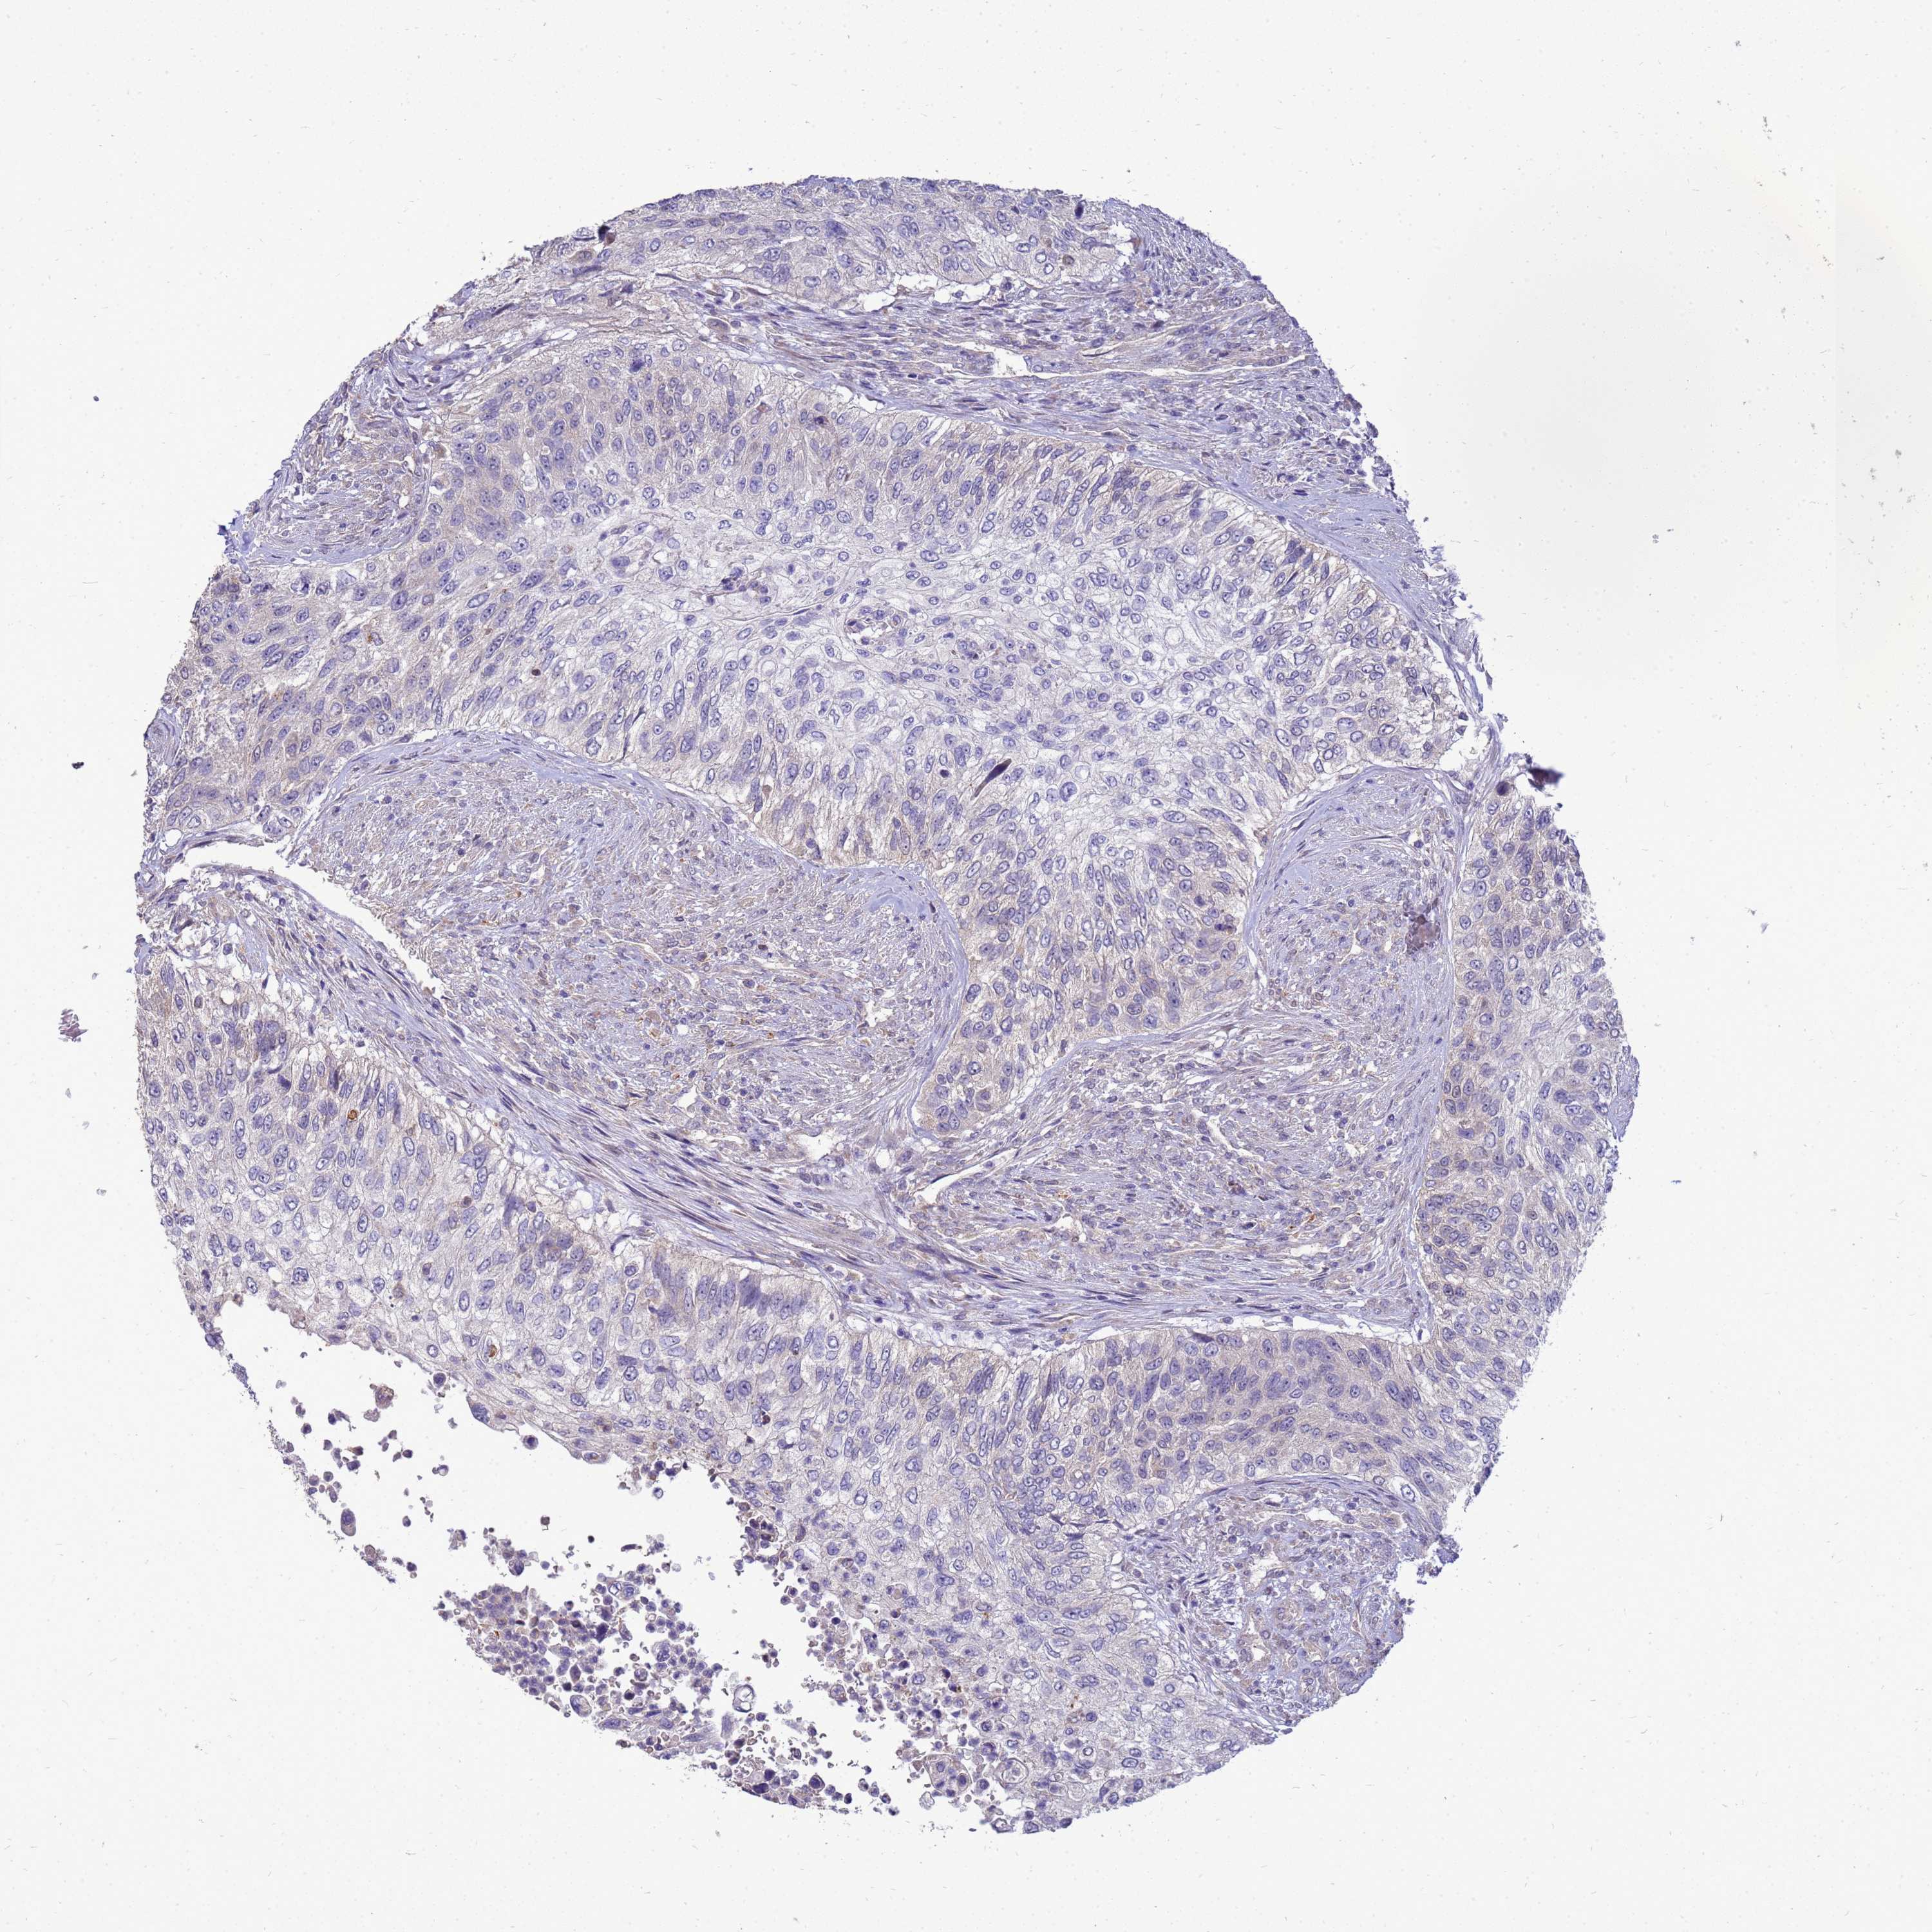

UROTHELIAL CANCER - Protein expressioni

A mouse-over function shows sample information and annotation data. Click on an image to view it in a full screen mode. Samples can be filtered based on level of antibody staining by selecting one or several of the following categories: high, medium, low and not detected. The assay and annotation is described here.

Antibody stainingi

Antibody staining in the annotated cell types in the current human tissue is reported as not detected, low, medium, or high, based on conventional immunohistochemistry profiling in selected tissues. This score is based on the combination of the staining intensity and fraction of stained cells.

Each image is clickable and will lead to virtual microscopy that enables deeper exploration of all samples and also displays staining intensity scores, fraction scores and subcellular localization as well as patient and tissue information for each sample.

Antibody HPA045537

Staining

High

Medium

Low

Not detected

Intensity

Strong

Moderate

Weak

Negative

Quantity

>75%

75%-25%

<25%

None

Location

Nuclear

Cytoplasmic/membranous

Cytoplasmic/membranous,nuclear

Urothelial carcinoma, High grade

Urothelial carcinoma, Low grade

Urothelial carcinoma, NOS